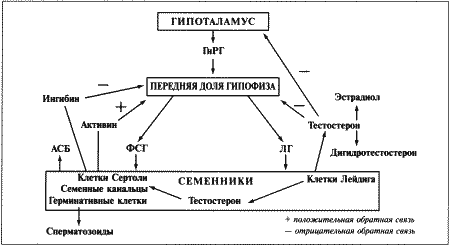

Стадия проэструса характеризуется развитием фолликулов под влиянием гонадотропных гормонов — лютеинизирующего (ЛГ) и фолликулостимулирующего (ФСГ), выделяемых передней долей гипофиза. Секреция этих гормонов регулируется гипоталамическим гонадотропинрилизинг гормоном (ГнРГ). У собак, так же, как и у других животных, вслед за пиком концентрации эстрадиола возникает (спустя сутки или чуть больше) пик концентрации ЛГ (фиг. 1.1). Таким образом, выброс ЛГ происходит всегда автоматически вслед за повышением активности фолликулов, вырабатывающих эстрадиол, и поскольку овуляция следует за возникающим без внешней стимуляции пиком концентрации ЛГ, ее называют спонтанной. Описанная ситуация разительно отличается от картины, которую можно наблюдать у кошек, для которых характерна индуцированная овуляция: у них выброс ЛГ и овуляция происходят вслед за коитусом. Насколько можно судить, у таких животных эстрадиол не способствует активации секреции ЛГ.

Повышение уровня ФСГ необходимо для стимуляции развития фолликулов и секреции эстрадиола, однако концентрация ФСГ в крови не достигает столь высоких значений, какие наблюдаются при пике ЛГ; это объясняют действием ингибина — белка, секретируемого фолликулами, который избирательно подавляет секрецию ФСГ Тем не менее ФСГ играет важную роль в созревании фолликулов и подготовке их к трансформации в желтые тела после овуляции. Начало трансформации фолликулярных клеток рассматривают как ключевой момент всего цикла, поскольку оно сопровождается преовуляторным повышением секреции прогестерона (фиг. 1.1), которое, по-видимому, играет ведущую роль в пусковом механизме овуляции и подтверждении эструса. Наблюдаемый у собак преовуляторный рост концентрации прогестерона нетипичен для других домашних животных, в частности для жвачных, у которых наступление эструса и овуляции происходит на фоне минимального уровня прогестерона. Однако преовуляторная концентрация прогестерона у собак все же относительно низка, и следует помнить, что назначение высоких доз прогестагенов в период проэструса вызывает отсрочку эструса и овуляции.